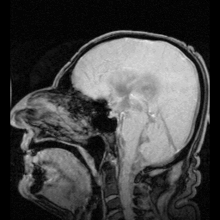

The scientific study of CT scans of the ventricles in the late 1970s gave new insight into the study of mental disorders. Researchers found that individuals with schizophrenia had (in terms of group averages) larger than usual ventricles. This became the first "evidence" that schizophrenia was biological in origin and led to a renewed interest in its study via the use of imaging techniques. Magnetic resonance imaging (MRI) has superseded the use of CT in research in the role of detecting ventricular abnormalities in psychiatric illness.